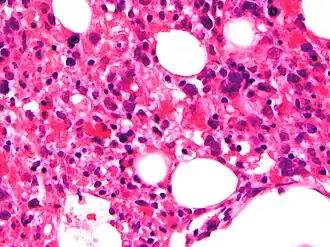

Description de cette image, également commentée ci-après

Moelle osseuse avec prolifération de macrophages contenant des globules rouges dans leurs cytoplasmes.

• Hémophagocytose dans la moelle osseuse ou dans la rate voire dans les ganglions lymphatiques. Ces cellules sont des macrophages avec présence d'éléments hématopoïétique dans le cytoplasme. Elles sont inconstamment retrouvées[7] et peuvent être également présentes en dehors de la lymphohistiocytose hémophagocytaire[8].